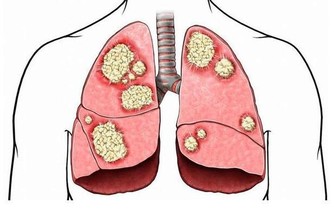

沒有了運動的支持,下肢的血液循環變慢,就容易讓血管變得擁堵。在臨床上也發現,靜脈曲張、下肢血栓的人,最好不要久坐、久站,更不要久躺,久躺在這3個方式當中,算是可以讓機體消耗熱量非常低的了,只會讓人越變越懶。

如果是比較嚴重的情況,還容易讓血管的血液流通變慢,增加血栓的發生危險。